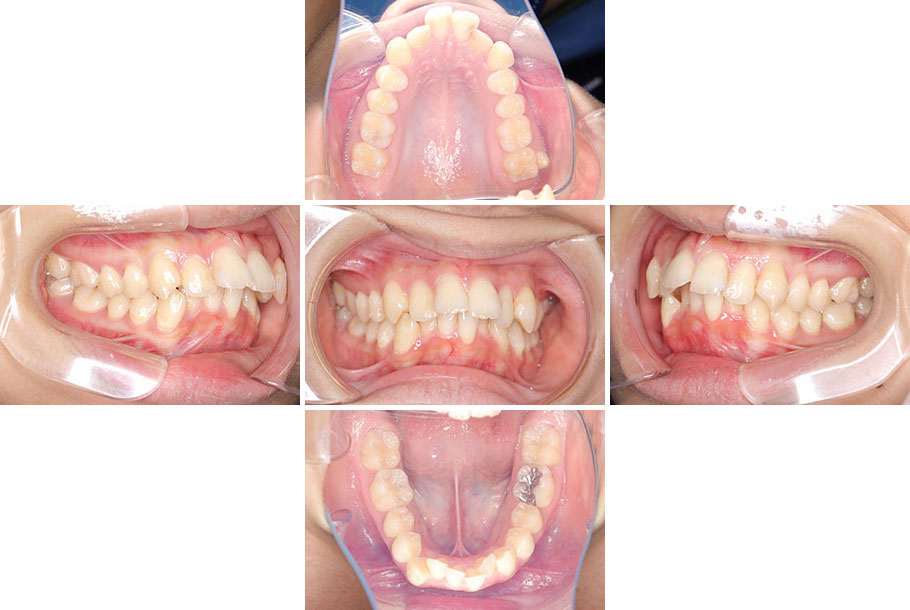

| 年齢・性別 | 10代女性 |

|---|---|

| 主訴 | 出っ歯、歯がガタガタしている |

| 症状 | 上顎前突、上下顎前歯叢生、過蓋咬合 |

| 装置 | ワイヤー矯正(マルチブラケット装置) |

| 抜歯 | 上顎左右2本抜歯(上顎両側第一小臼歯) |

| 費用 | 880,000円(税込) |

| 治療期間 | 1年4か月 |

| 副作用 (リスク) |

治療中の違和感・痛み、歯根吸収、歯周病、虫歯、歯肉退縮、歯髄壊死が認められる可能性があるが、この症例については認められなかった。 |